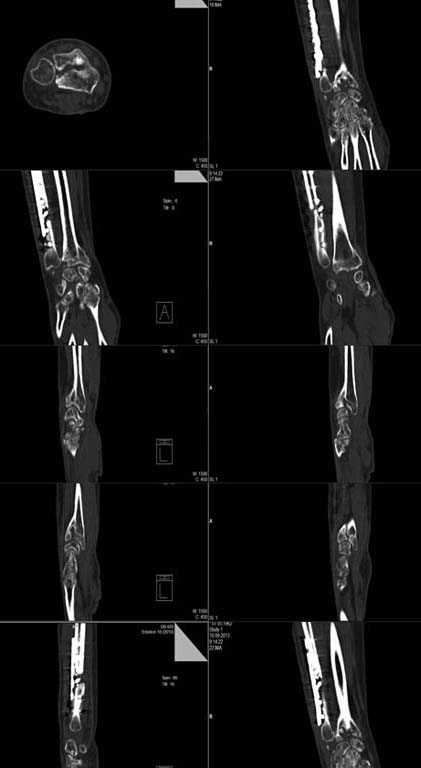

[Ortho] Последствия травмы и лечения перелома предплечья

КТ

Имя     : CT forearrm.jpg